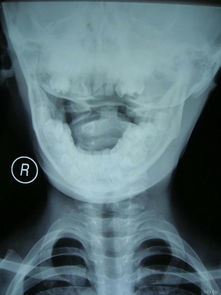

寰枢关节半脱位是指颈椎的第一节(寰椎)、第二节(枢椎)之间的关节失去正常的对合关系。

第一颈椎又名寰椎,由前弓、后弓和侧块构成,第二颈椎又名枢椎,上方有齿状突与第1颈椎构成寰枢关节。

颈部旋转功能约有50%发生在寰枢关节。

其脱位一般有4种情况:前脱位(寰椎横韧带断裂),后脱位,齿状突基底部骨折及。